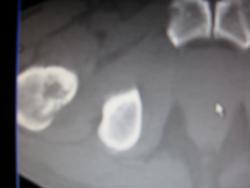

Сдаюсь - метастазы (ну если миеломную болезнь исключили, конечно)

Честно миеломную болезнь не исключали. Просто здесь тоже есть первичный очаг + клиника. Более полугода назад - гастрэктомия, верификация. Буквально все эти изменения болят именно в тех местах. Боли появились примерно месяца два назад за последние несколько месяцев (3-6?) похудел примерно на 10 кг. Слегка смущал позвонок - D12 - на МРТ поясн. отдела, сделанном пару недель назад (делали не у нас), написали грубая грыжа Шморля на ихних картинках на неё и похоже а вот на наших я всё-таки склонился к мтс.

Про миеломную, это я так, только из-за множественности, чтоб не забывать. На самом деле, конечно, картина мтс

миелома была сегодня чуть позже кину фото